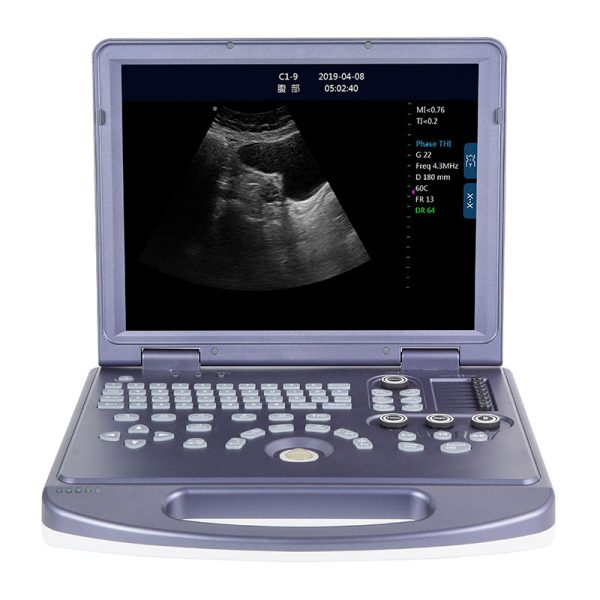

Máquina de ultrasonido portátil en blanco y negro RC-BW580

El ultrasonido portátil RC-BW580 es un equipo diagnóstico confiable diseñado para ofrecer imágenes precisas en una amplia variedad de entornos clínicos. Con una pantalla LED de 12 pulgadas y modos de imagen versátiles, como B, 2B, 4B, M y B&M, permite evaluar estructuras anatómicas con claridad y eficiencia. Su sonda multifrecuencia proporciona un rango de aplicaciones clínicas, desde abdomen y obstetricia hasta tejidos blandos y exploraciones musculoesqueléticas.

El RC-BW580 está equipado con reconocimiento de 65 marcas corporales, lo que facilita una mayor exactitud durante el examen y mejora el flujo de trabajo del profesional. Su batería de larga duración (3–5 horas) lo convierte en una solución ideal para clínicas móviles, consultorios, zonas rurales y atención domiciliaria.

La portabilidad del sistema, junto con sus puertos USB y entradas para sondas adicionales, garantiza flexibilidad y compatibilidad con diferentes configuraciones clínicas. Su diseño intuitivo y soporte multilingüe permiten un uso sencillo incluso en entornos de alta demanda. En conjunto, el RC-BW580 es una herramienta esencial para médicos y especialistas que requieren un ultrasonido práctico, eficiente y accesible.

El RC-BW580 es una máquina de ultrasonido portátil en blanco y negro diseñada para ofrecer diagnóstico eficiente en diversos entornos clínicos. Cuenta con una pantalla LED de 12 pulgadas, modos de imagen versátiles (B/2B/4B/M/B&M) y soporte multilingüe, lo que facilita su uso en distintos escenarios médicos. Su sonda multifrecuencia y capacidad para reconocer 65 marcas corporales permiten obtener imágenes precisas. Además, su batería de larga duración (3-5 horas) y puertos USB y de sonda hacen que sea una herramienta portátil y confiable para profesionales de la salud.